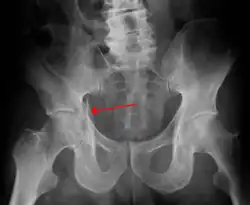

Acetabular fracture as seen on plain X-ray

1. Pelvis with both hips antero posterior view. This view shows six important landmarks of the acetabulum, specifically:

• Pelvic brim

• Ilio ischial line

• Tear drop

• Anterior wall

• Posterior wall

• Weight bearing dome